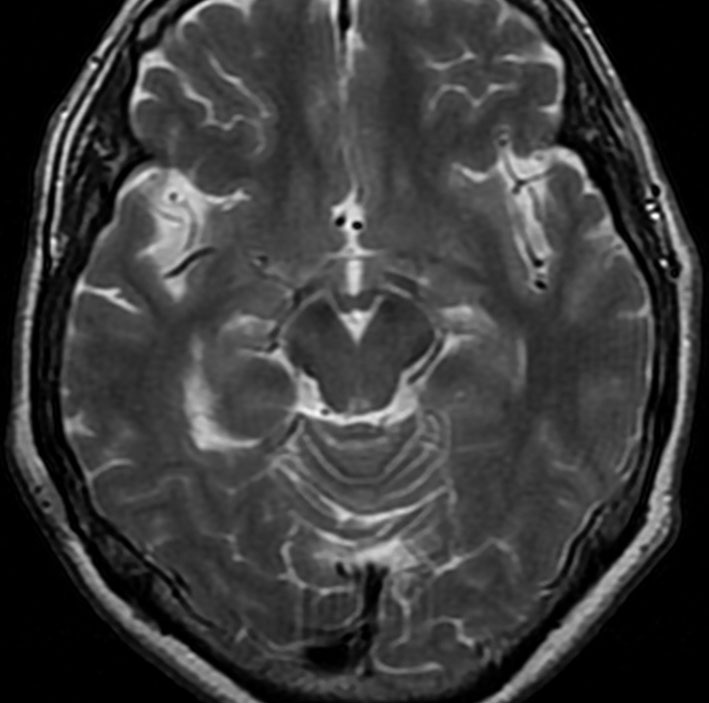

これは11歳の子供で偶然発見された右側脳室くも膜のう胞です。無症状で変化しませんからほっておきます。右のモンロー孔に狭窄があるために右側脳室だけの停止性水頭症になっています。